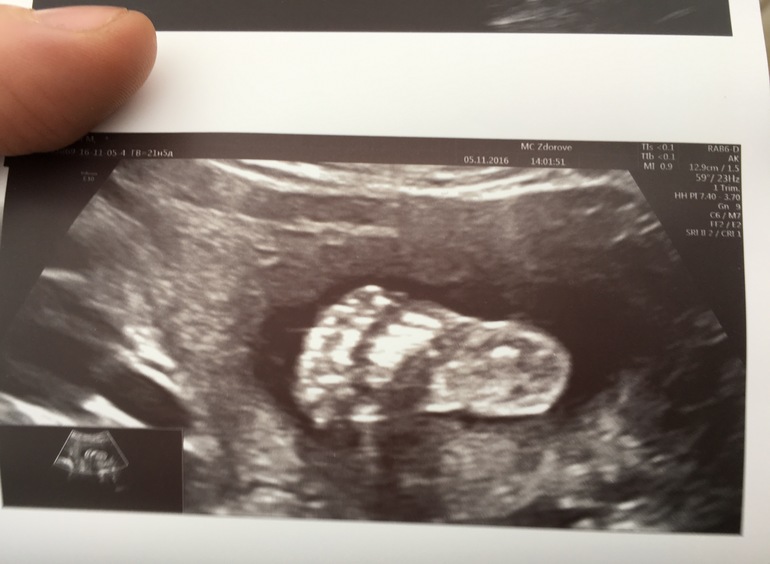

Второй скрининг пройден !)

УЗИ, КТГ, доплерВсе у нас хорошо , сроку соответсвует. Вес 413 грамм. Сегодня 21.6 недель . Все отлично , только пуповина 2 сосуда. Но врач говорит что все нормально. Мужичок мой показал себя во всей красе😄Пристала узистка к нашему маленькому носу . 5 мм. К сыну первому тоже я помню она прикопалась из-за маленького носа , и ниче , родился с аккуратненьким носом )